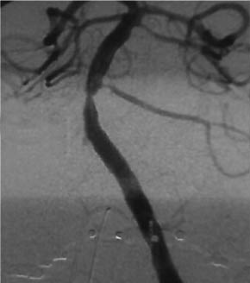

Figure. Cerebral ang... - Click to enlarge in new windowFigure. Cerebral angiogram showing stenosis.